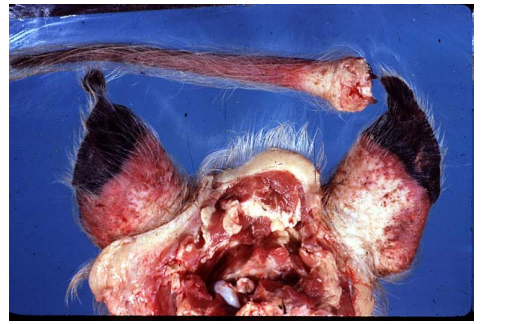

What is happening here and give a possible cause

Wet gangrene, mammary gland (longitudinal section through the teat), sheep.

Staphylococcal infection caused the gangrenous mastitis